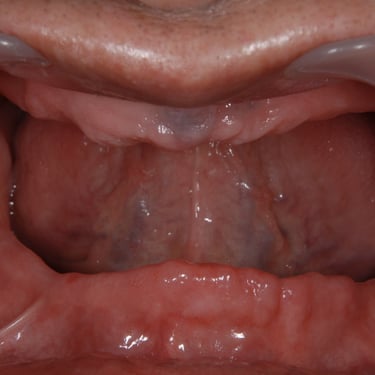

Edentulismo completo

El edentulismo completo es la ausencia total de dientes en una o ambas arcadas.

Los pacientes tienen dificultad para masticar, hablar y pueden sentirse incómodos con su apariencia.

El tratamiento puede incluir la colocación de una prótesis completa sobre implantes, proporcionando una solución fija y estable